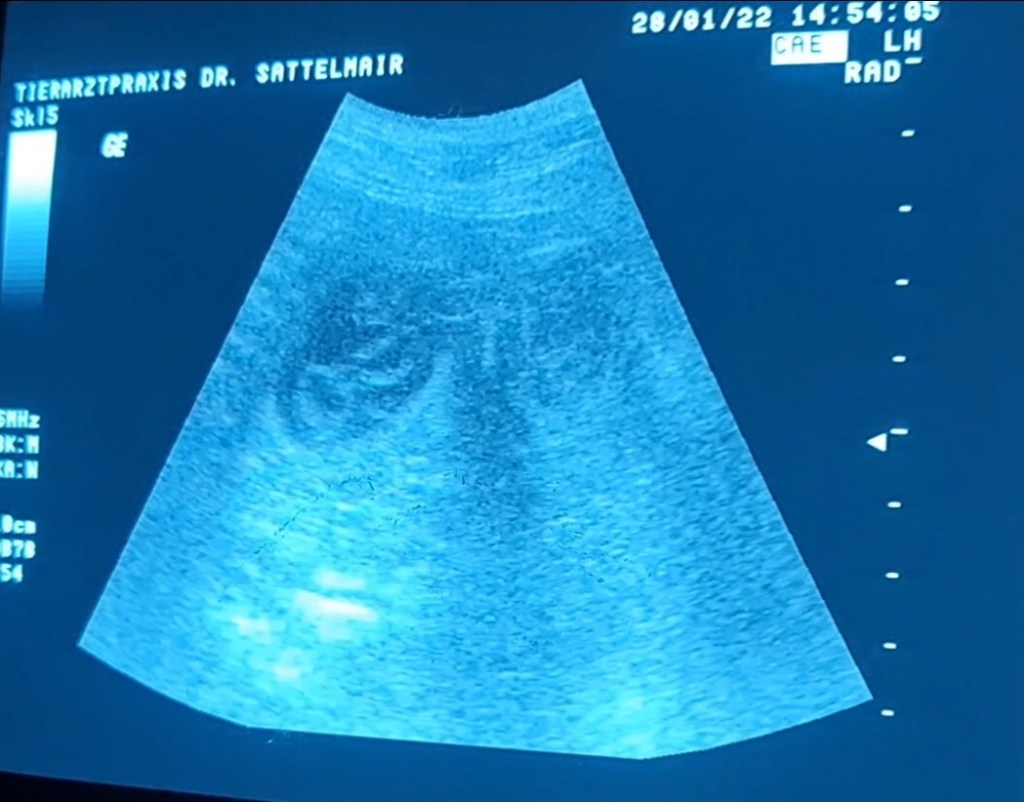

Hier der Beweis:

Das Bäuchlein, Tag 32 von ca. 63